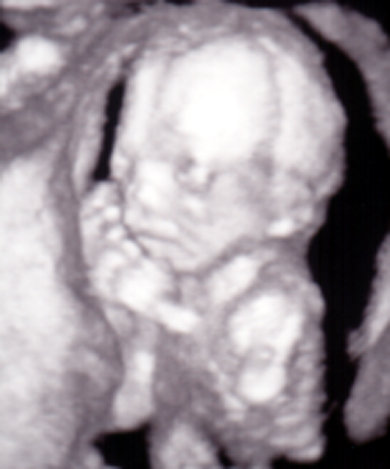

Anna 18 és fél hetesen: Kép Kép